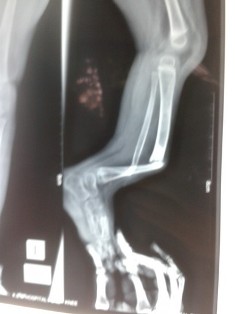

This is a relatively rare condition in which the parents will complain of anterior or anterolateral bending of tibia (shin bone). The bowing can become apparent around 6 months of age. It goes on progressing and then the child will present with a fracture. There are mainly two types. Dysplastic type in which there is narrowing and sclerosis and cystic type in which there are cyst like areas. It may be associated with neurofibromatosis.

The non union site needs to be excised and an intramedullary rod is inserted to prevent refracture. Bone grafting is also required. The management of this condition is difficult and repeated surgery may be required. In older children Ilizarov method for compression and lengthening can be used to attain union. Newer elongating rods have also been used with good results.